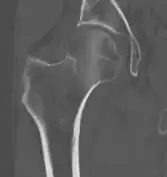

4) Данные рентгенологического обследования — выполняется рентгенография тазобедренного сустава в прямой проекции. Наличие линии перелома на рентгенограмме служит окончательным, объективным подтверждением предварительно выставленного диагноза. Иногда для постановки диагноза может потребоваться магнитно-резонансная томография или компьютерная томография.

В большинстве случаев достаточно выполнения рентгенограммы в прямой проекции. В ситуациях, когда есть подозрение на перелом шейки бедра, но оно не выявлено на рентгеновском снимке, следующим методом исследования является КТ. В редких случаях для подтверждения диагноза используется МРТ - диагностика.

Случай, демонстрирующий возможный порядок исследования изначально незаметных проявлений: